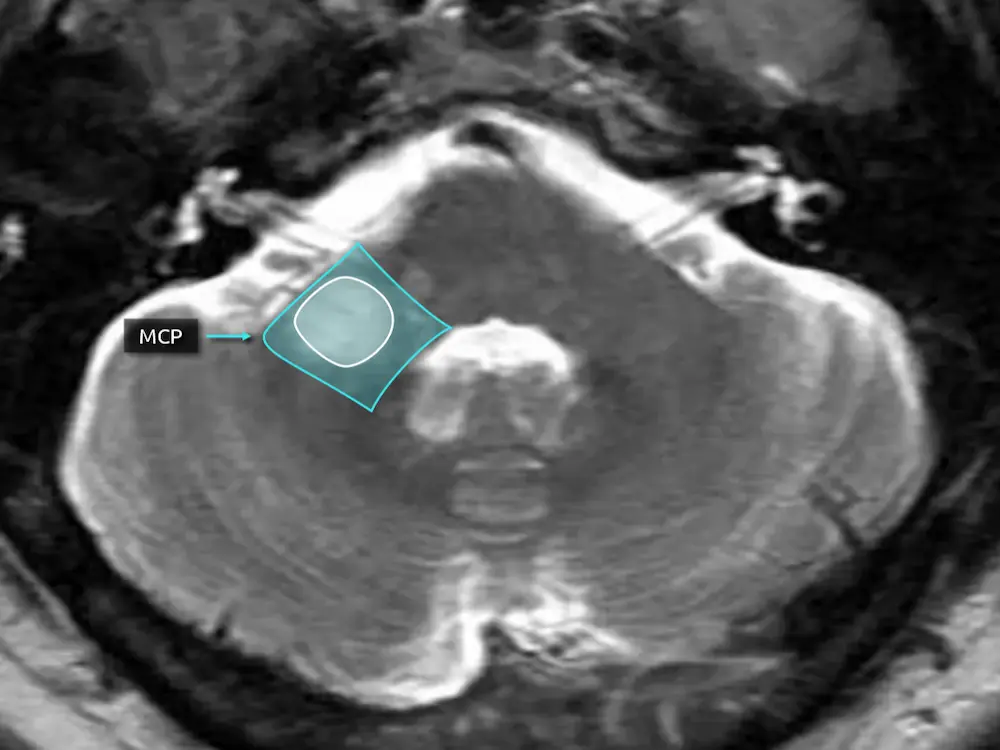

The cerebellum receives arterial supply from the posterior circulation (Figure 7). Above the level of the middle cerebellar peduncles, the majority of the cerebellum is supplied by the superior cerebellar artery (SCA). Below, the majority is supplied by the posterior inferior cerebellar artery (PICA). The anterior inferior cerebellar artery (AICA) has a smaller contribution, supplying the middle cerebellar peduncles and the flocculus. Note the AICA does not classically contribute to the vermis.

In reality, the boundaries of these territories are not so clear cut and there is significant variation. The AICA and PICA are in balance with each other, such that a patient with a small PICA will have a larger AICA that supplies a larger portion of the inferior cerebellar hemispheres (i.e. AICA-PICA balance or AICA-PICA dominance). There is also a balance of supply to the vermis between the SCA and PICA.